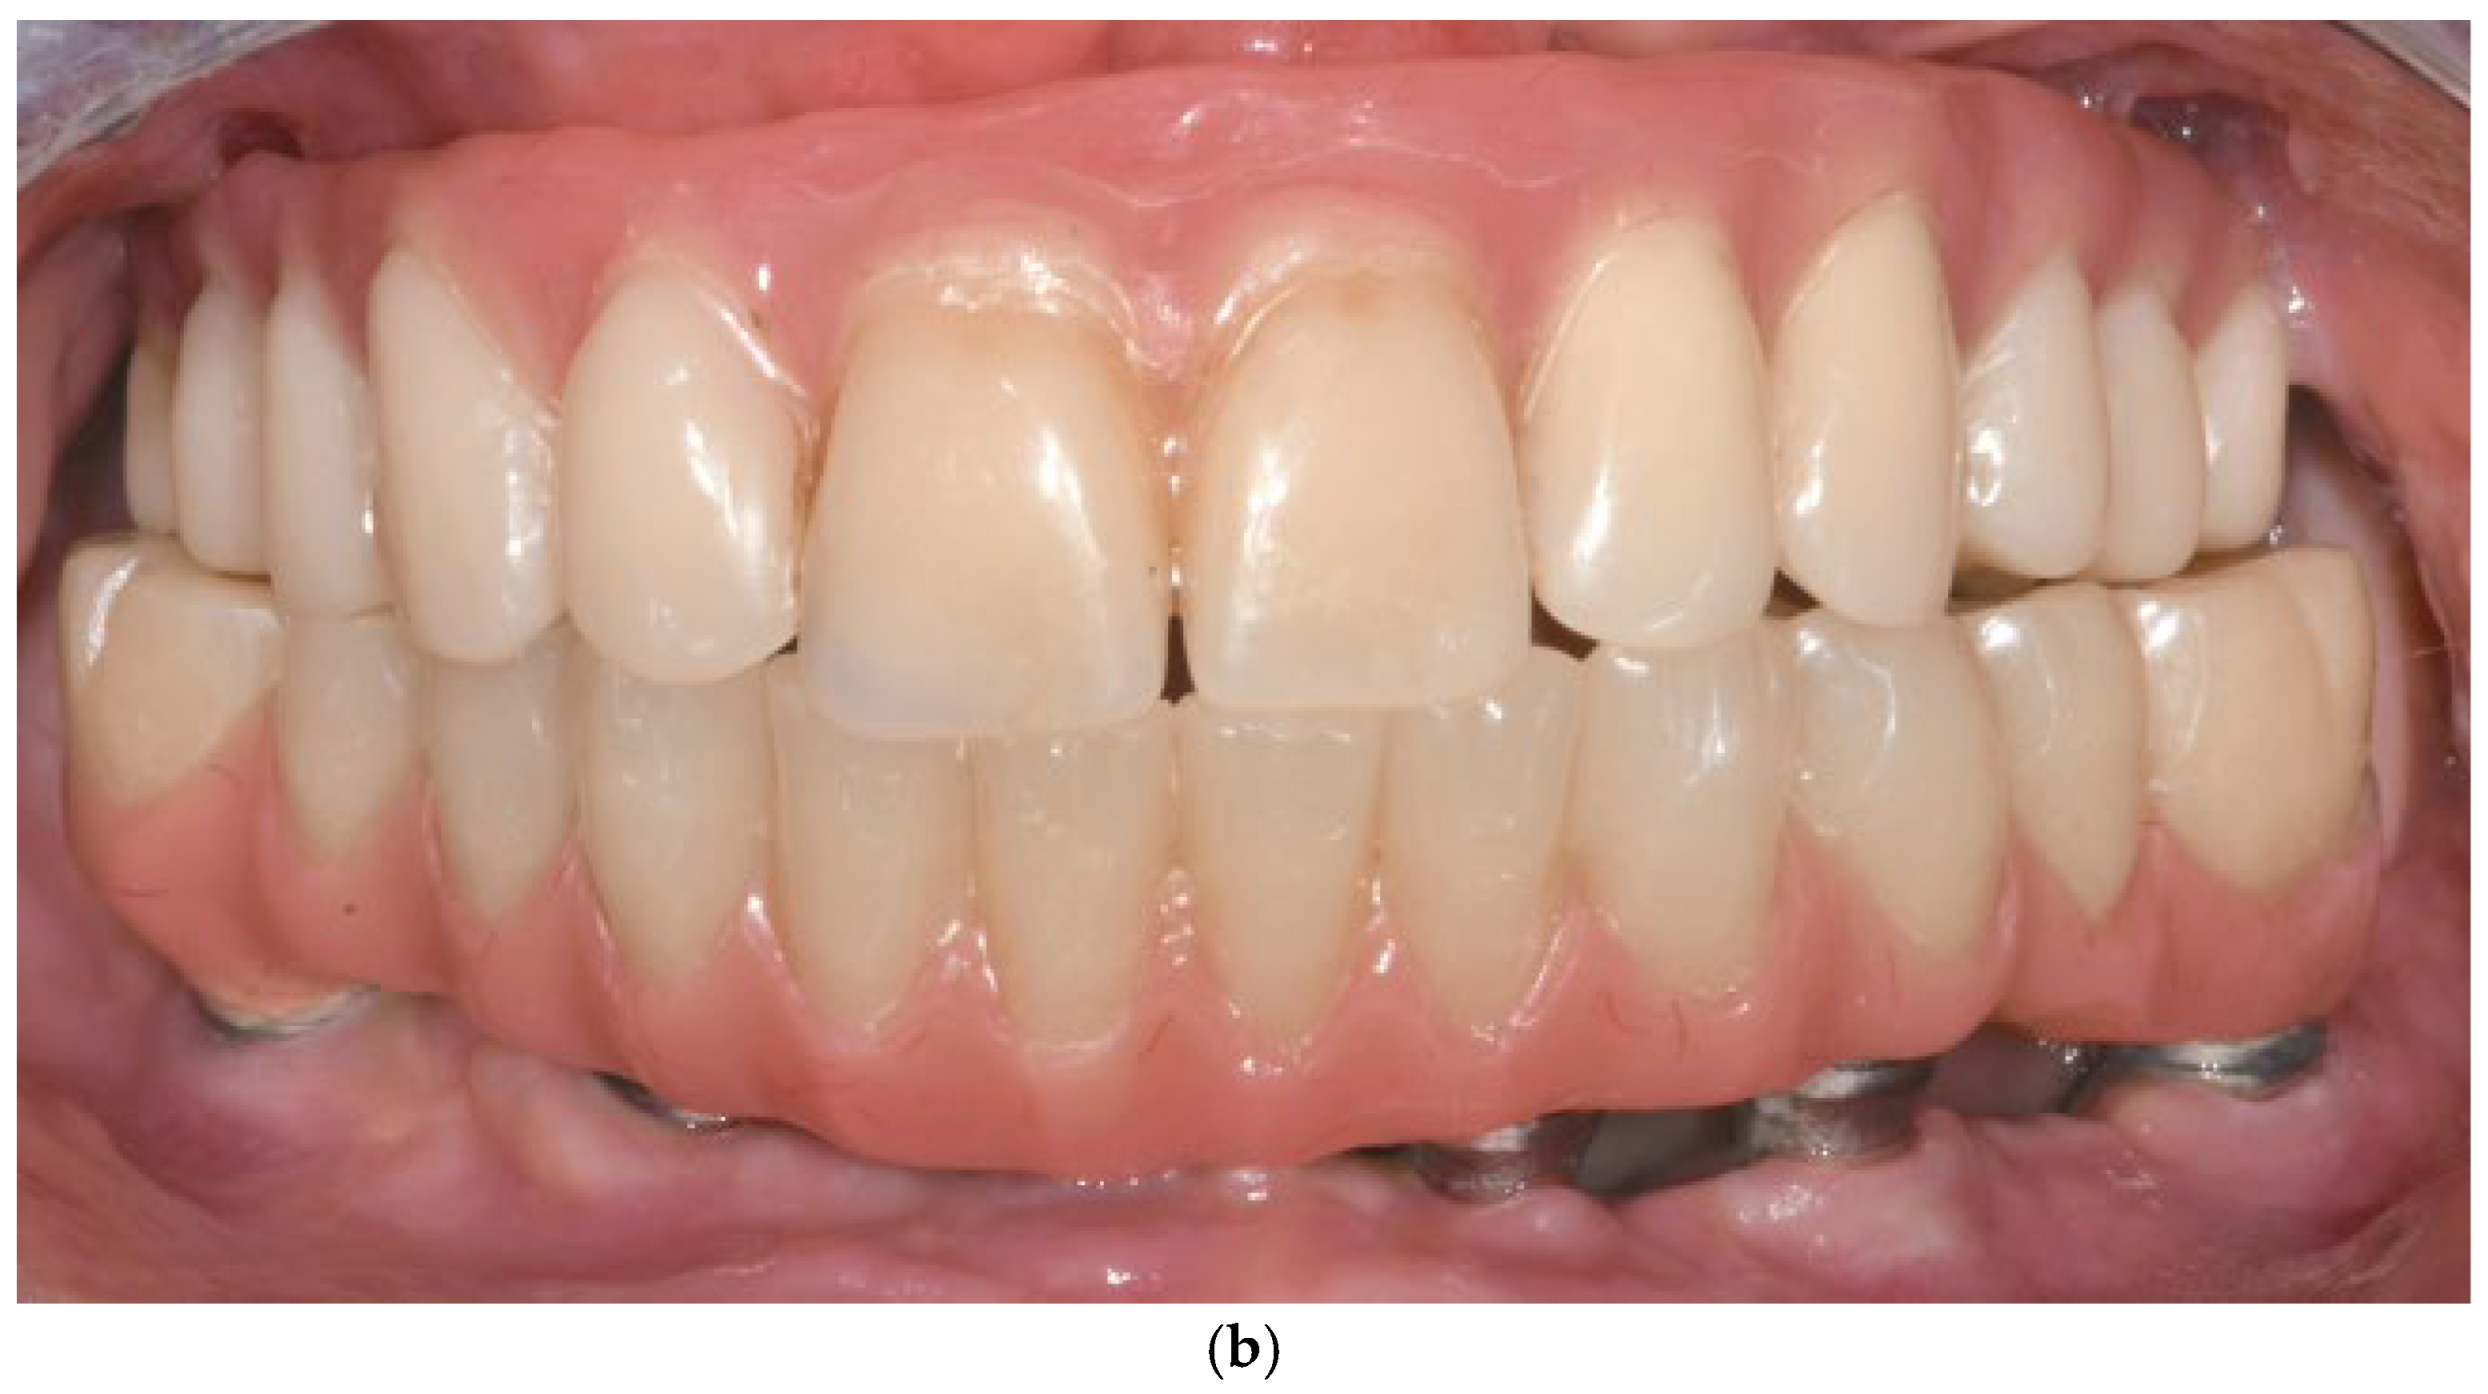

3.11. Case Series

3.11.1. Patient Demographics and Clinical Characteristics

3.11.2. Surgical and Prosthetic Protocol

4.5. Prosthetic Design

- Immediate loading with provisional prosthesis (24–72 h post-op). (Supports soft tissue healing and functional rehabilitation).

- Final prosthesis placement after 4 months. (Ensures tissue maturation and long-term durability).

- Passive fit and absence of considerable cantilevers. (Prevents biomechanical overload and prosthetic complications) [52].